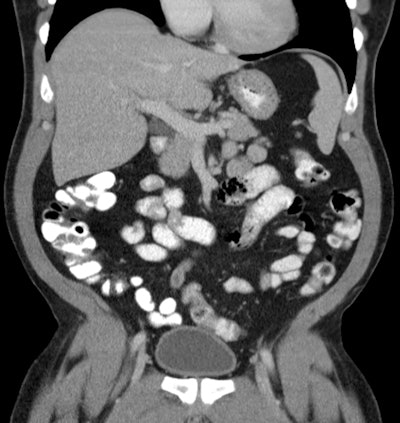

For most patients this protocol provides relatively uniform enhancement of the stomach and small bowel, although significant differences can be seen in some patients.

The degree of colonic enhancement is variable. If gastric opacification is of particular concern, a greater proportion of the contrast mixture should be saved for ingestion just prior to scanning, or 250 mL of an additional mixed bottle should be ingested just before scanning.